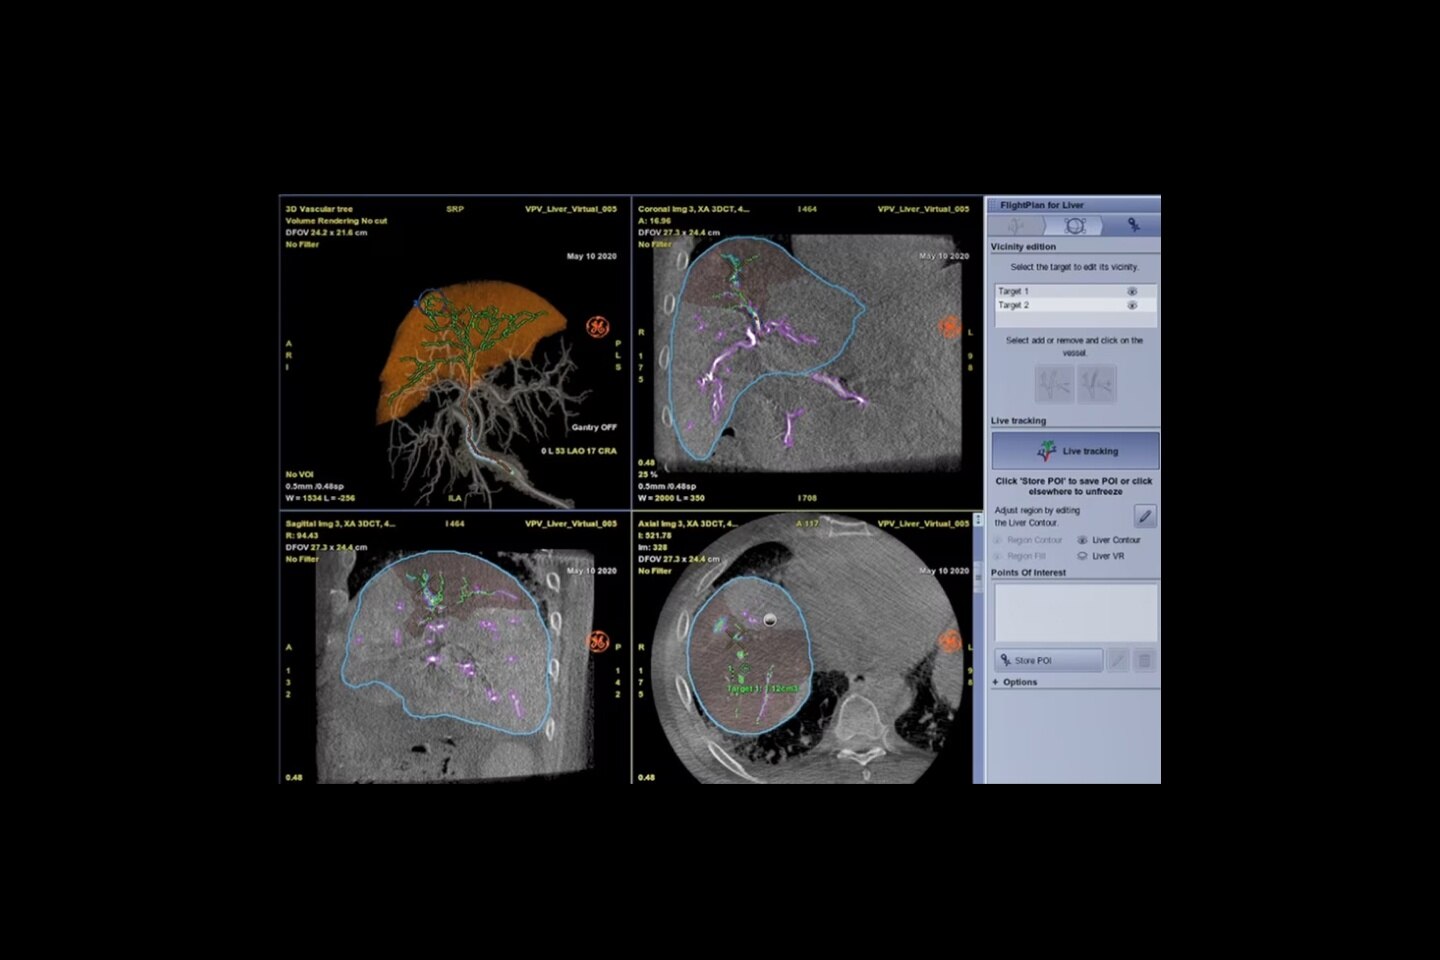

Análisis preciso

OEC 3D utiliza la tecnología de imagen comprobada de la AW de GE Healthcare para proporcionar una experiencia de imagenología 3D premium. Analice imágenes con el conjunto de herramientas de imagenología 3D Volume Viewer, incluyendo el Modo Multioblicuo, desplazándose por todos los 512 cortes, nivelación de ventana, zoom y más.

Interfaz abierta

Con una plataforma abierta, el OEC 3D puede integrarse perfectamente con los sistemas de navegación y robótica. El puerto dedicado de OEC Open puede exportar datos 3D de alta fidelidad configurados para sistema de navegación o robótica que aceptan imágenes DICOM.